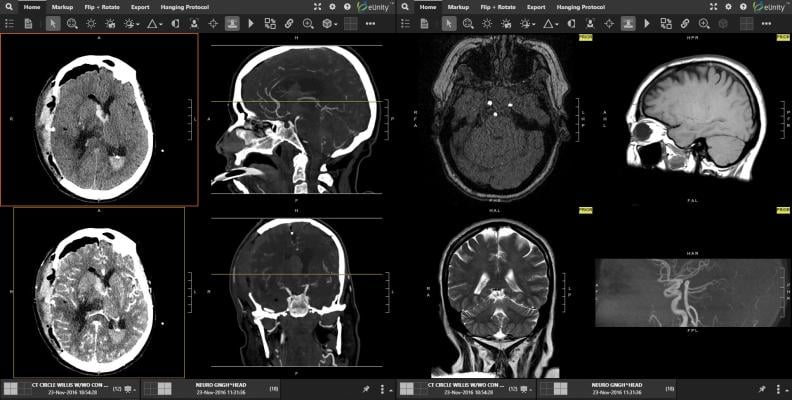

April 11, 2024 — Mach7 Technologies, a company specializing in innovative medical imaging and data management solutions for healthcare organizations, announced its participation in the Veterans Health Administration's (VHA) National Teleradiology Program (NTP). As part of this multi-phased contract, Mach7 will provide its well-established Vendor Neutral Archive (VNA) and industry leading eUnity Enterprise Diagnostic Viewer to help form the core workflow of the NTP NextGen Picture Archiving and Communication System (PACS) architecture.

The VHA offer was awarded to Frontier Acquisitions, LLC, which is a prime vendor based out of San Antonio, Texas. Frontier selected Nuance to provide Voice Recognition and Diagnostic Radiology Workflow, Mach7 Technologies as the Diagnostic Viewer and Vendor Neutral Archive, Blackford (blackfordanalysis.com) to incorporate Adaptive Intelligence (AI) Technology and Microsoft Corporation to provide it's Azure Cloud Computing Platform.

Within the framework of this implementation, Mach7 brings to the forefront core market differentiators and value around the adoption of advanced imaging technologies that provide unique independence and long-term sustainability. The VHA NTP award, through Frontier, is a tremendous opportunity for Mach7 to deliver and showcase its unique Enterprise Imaging Solution with strong interoperability to the VHA's existing and newly deployed imaging systems. This distinctive enterprise-driven architecture will grant the VHA the ability to leverage its existing medical systems while not being tied to a single vendor's proprietary ecosystem.